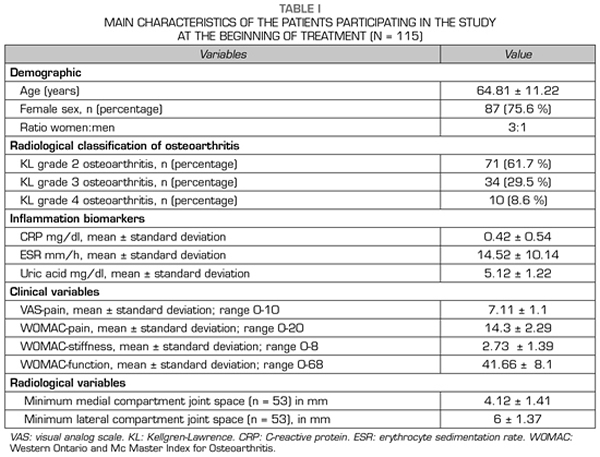

115 patients were evaluated in this study. The mean age of the patients was 64.81 ± 11.22 years. Female patients accounted for 75.6 % (n = 87), while male patients accounted for 24.4 % (n = 28), with a female: male ratio of 3:1 (Table I).

The most frequent radiological grade was KL grade 2 (n = 71; 61.7 %), followed by KL grade 3 (n = 34; 29.5 %) and KL grade 4 (n = 10; 8.6 %) (Table I).